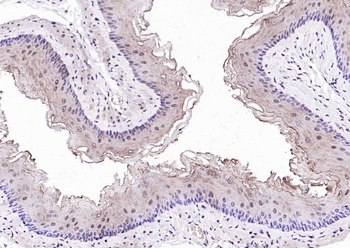

CDKN1A Antibody

Catalog Number: orb682382

| Description | CDKN1A Antibody |

| Target | CDKN1A |

200 μl, 50 μl, 100 μlCDKN1A/p21 Rabbit Polyclonal Antibody [orb11203]

FC, ICC, IF, IHC-Fr, IHC-P

Bovine, Canine, Gallus

Human, Mouse, Rat

Rabbit

Polyclonal

Unconjugated

50 μl, 100 μl, 200 μlPhospho-PAK6 (Ser560) Rabbit Polyclonal Antibody [orb6634]